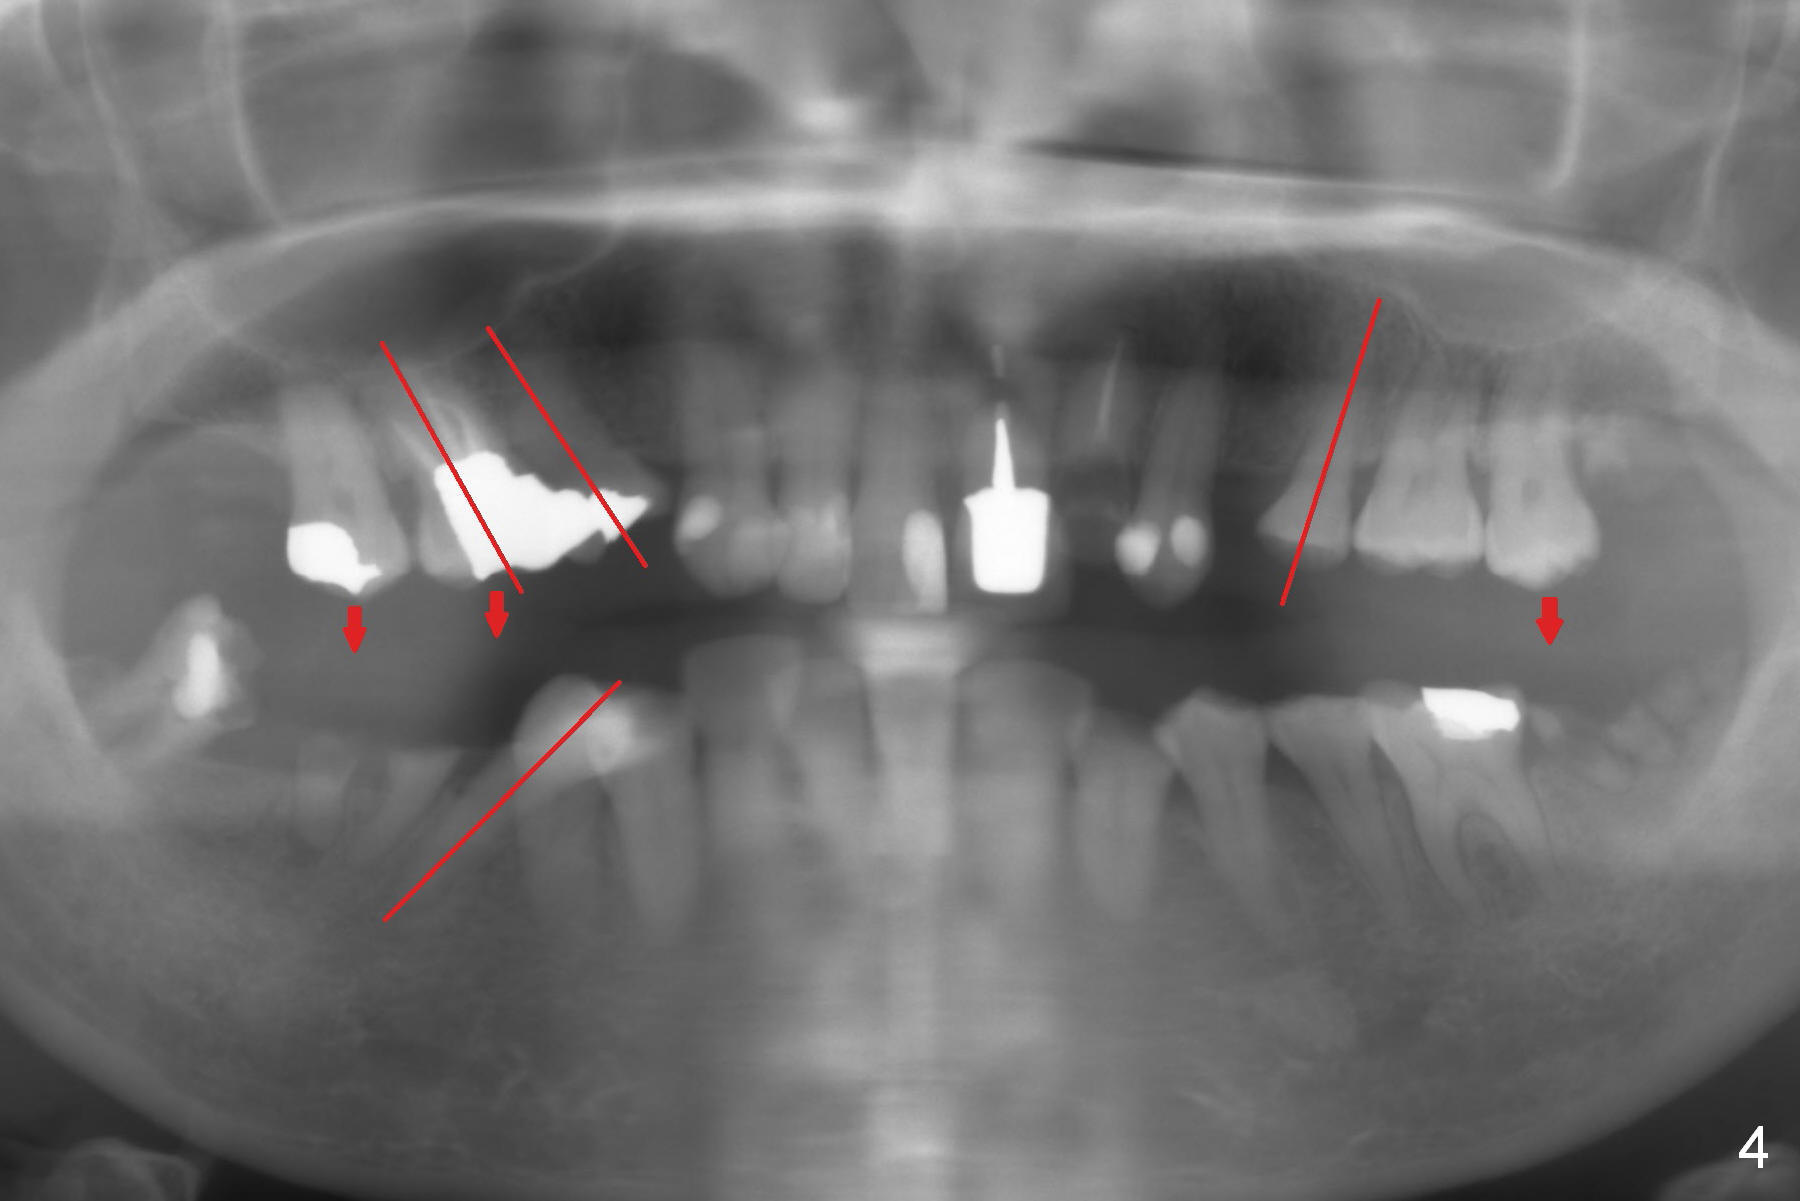

A fifty five year old lady requests implant restoration for the upper left lateral incisor after the crown fractures (Fig.3*). X-ray in Fig.1,2,4 were taken before loss of the crown. The biggest issue is the narrow space of this lateral mesiodistally (Fig.3).